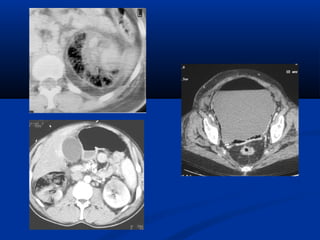

 CT :CT :

 Khảo sát hình thái và chức năngKhảo sát hình thái và chức năng

 KT nhạy nhất để tìm ổ nhiễm trùng : dùngKT nhạy nhất để tìm ổ nhiễm trùng : dùng

dynamic CT, có hình ảnh giữ thuốc cản quang tạidynamic CT, có hình ảnh giữ thuốc cản quang tại

thì muộn.thì muộn.

 Dấu hiệu gián tiếp: đường bờ mờ, dày mạc thận,Dấu hiệu gián tiếp: đường bờ mờ, dày mạc thận,

thâm nhiễm mỡ quanh thận.thâm nhiễm mỡ quanh thận.

Thận đồ

Thì muộn

Thì vỏ - tủy